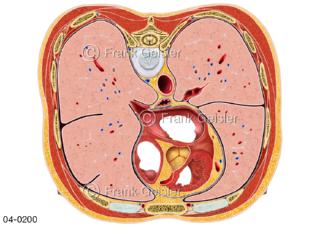

Bildergalerie Topografie Organe

Bilder zur topografischen Anatomie, die Lage der Organe und die Strukturen nach ihren räumlichen Lagebeziehungen zueinander, Übersicht der inneren Organe im Kopf und im Rumpf, Topografie der Organe im Brustraum (Thorax) und im Bauchraum (Abdomen)